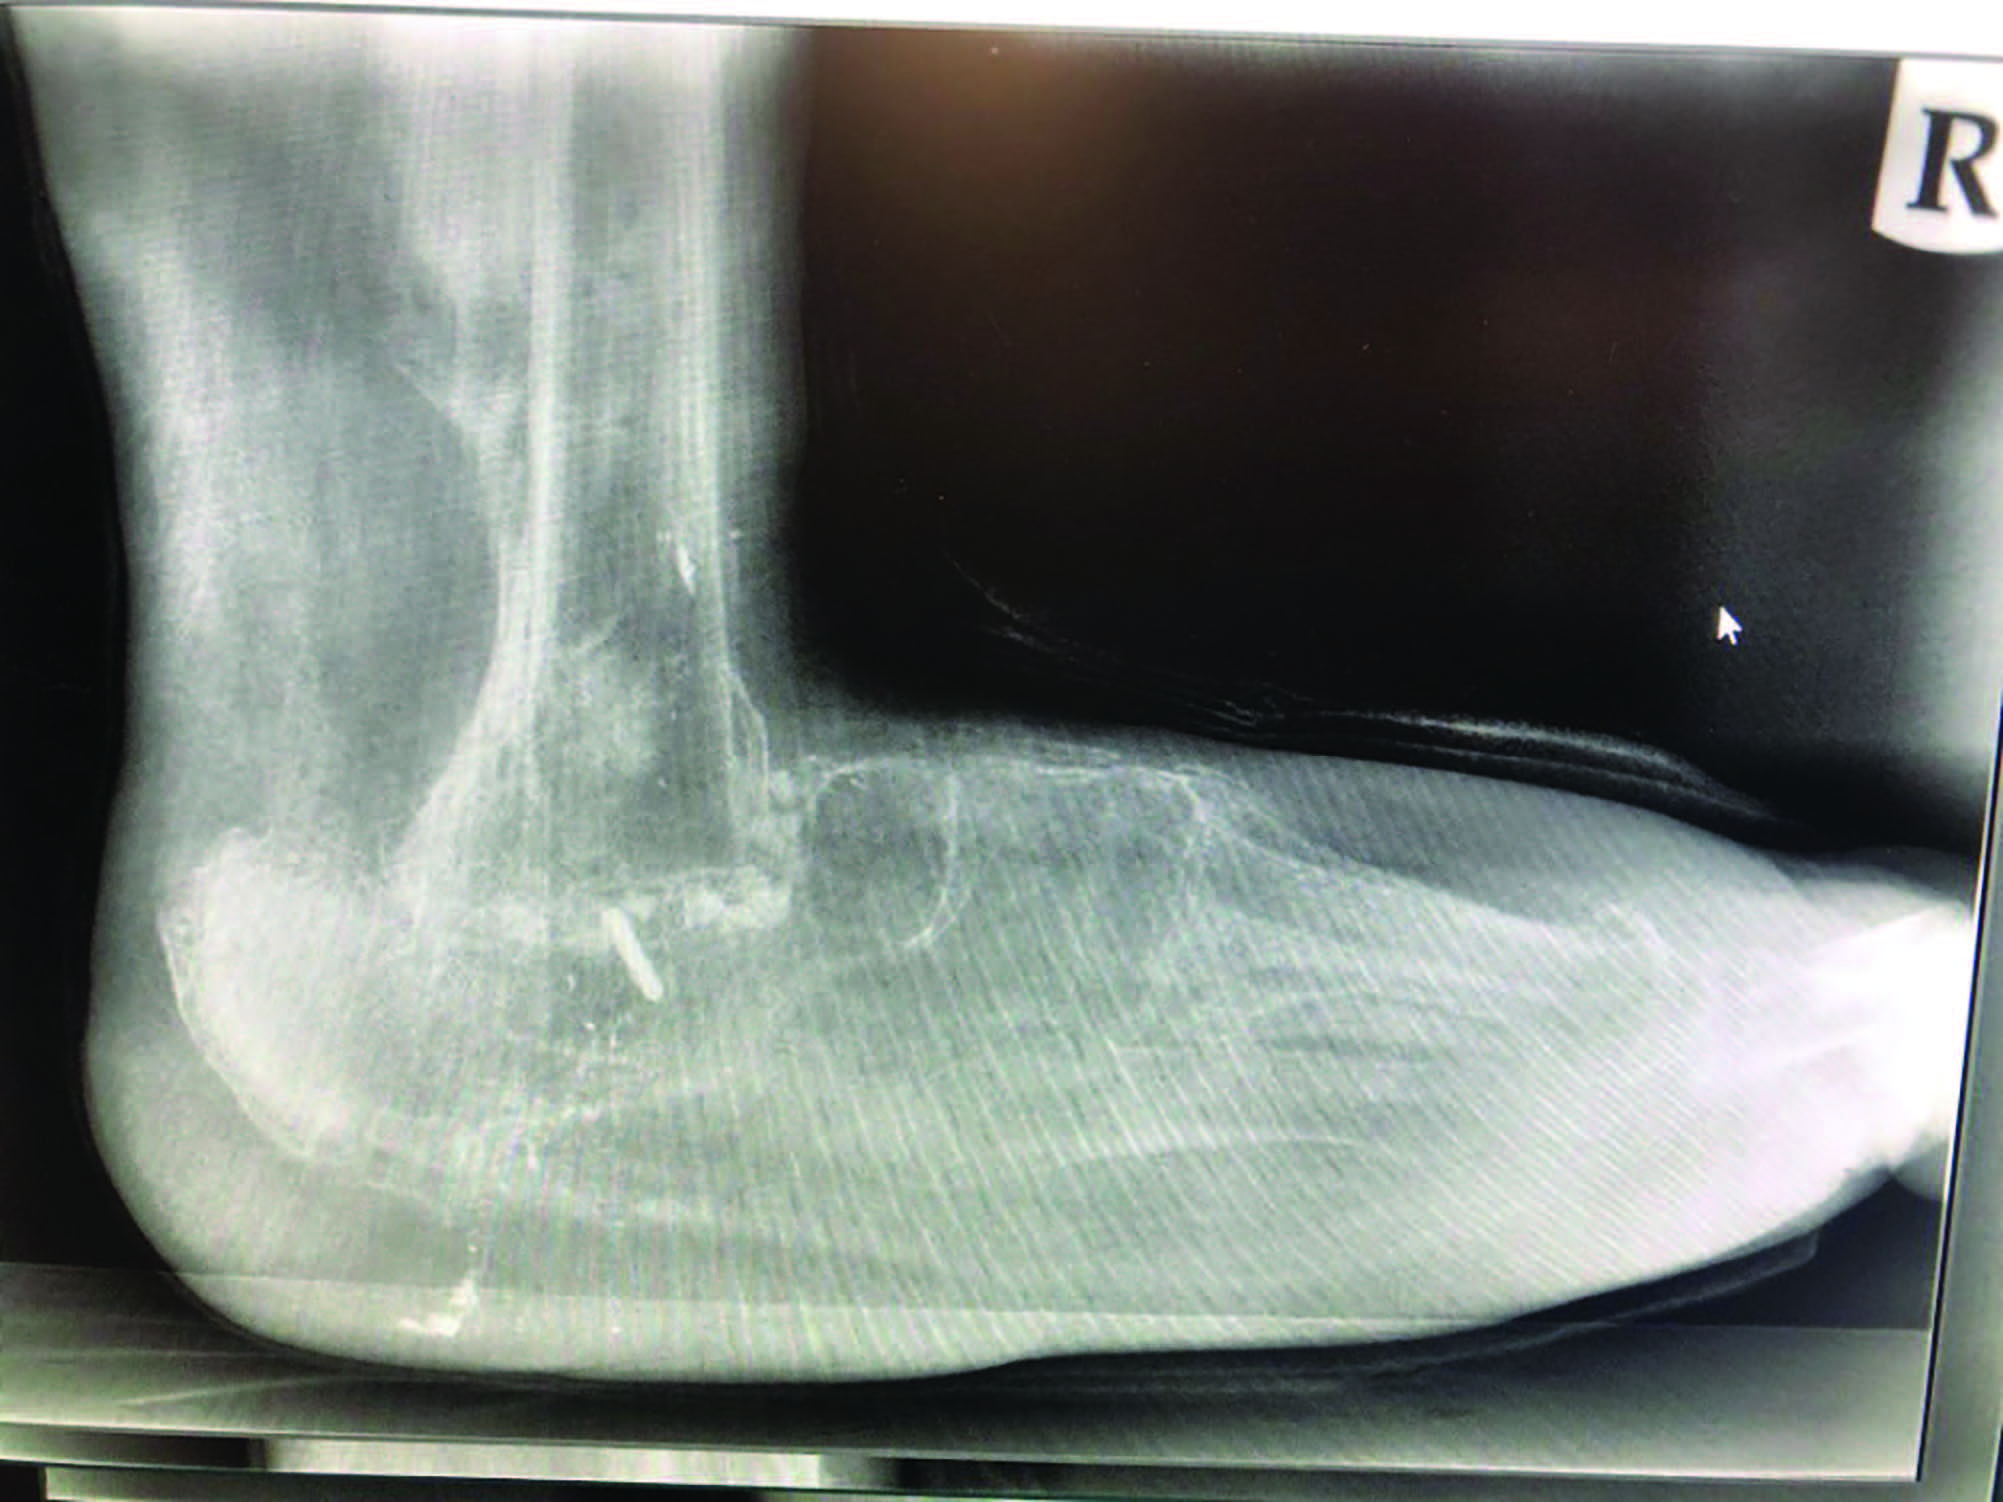

William P. Grant, DPM popularized the concept of beaming in Charcot,2 and subsequent modification and perfection continues through more recent literature.3 Beaming the medial column with large diameter screws was first mentioned at the American College of Foot and Ankle Surgeons conference in 1997.4 Since then, literature supports 2 to 3 beams in the medial and lateral columns, and the hindfoot for more stability.2 Beaming the midfoot and hindfoot acts like reinforcement rods, or rebar, to accept compressive and tensile loads and compensate for inadequacies of native structures.

Grant and colleagues looked at beaming of the medial column only versus medial and lateral with and without subtalar joint arthrodesis.2 They found that with medial column beaming alone, the mechanical advantages of the posterior tibial tendon increased, which led to increased plantar lateral pressure and collapse of the non-beamed lateral column. They also found that locking the subtalar joint (via either arthrodesis or arthroereisis) further stabilized transverse and frontal plane torsion.2 Other studies confirmed that this 3-beam construct seems to be the most stable, with less chance of a secondary collapse in the foot.3,5 Other advantages of beaming include no cortical stress on the bone (unlike plates/screws), allowing for fixation beyond the site of collapse, making it more stable, and no exposed hardware in the presence of dehiscence.3